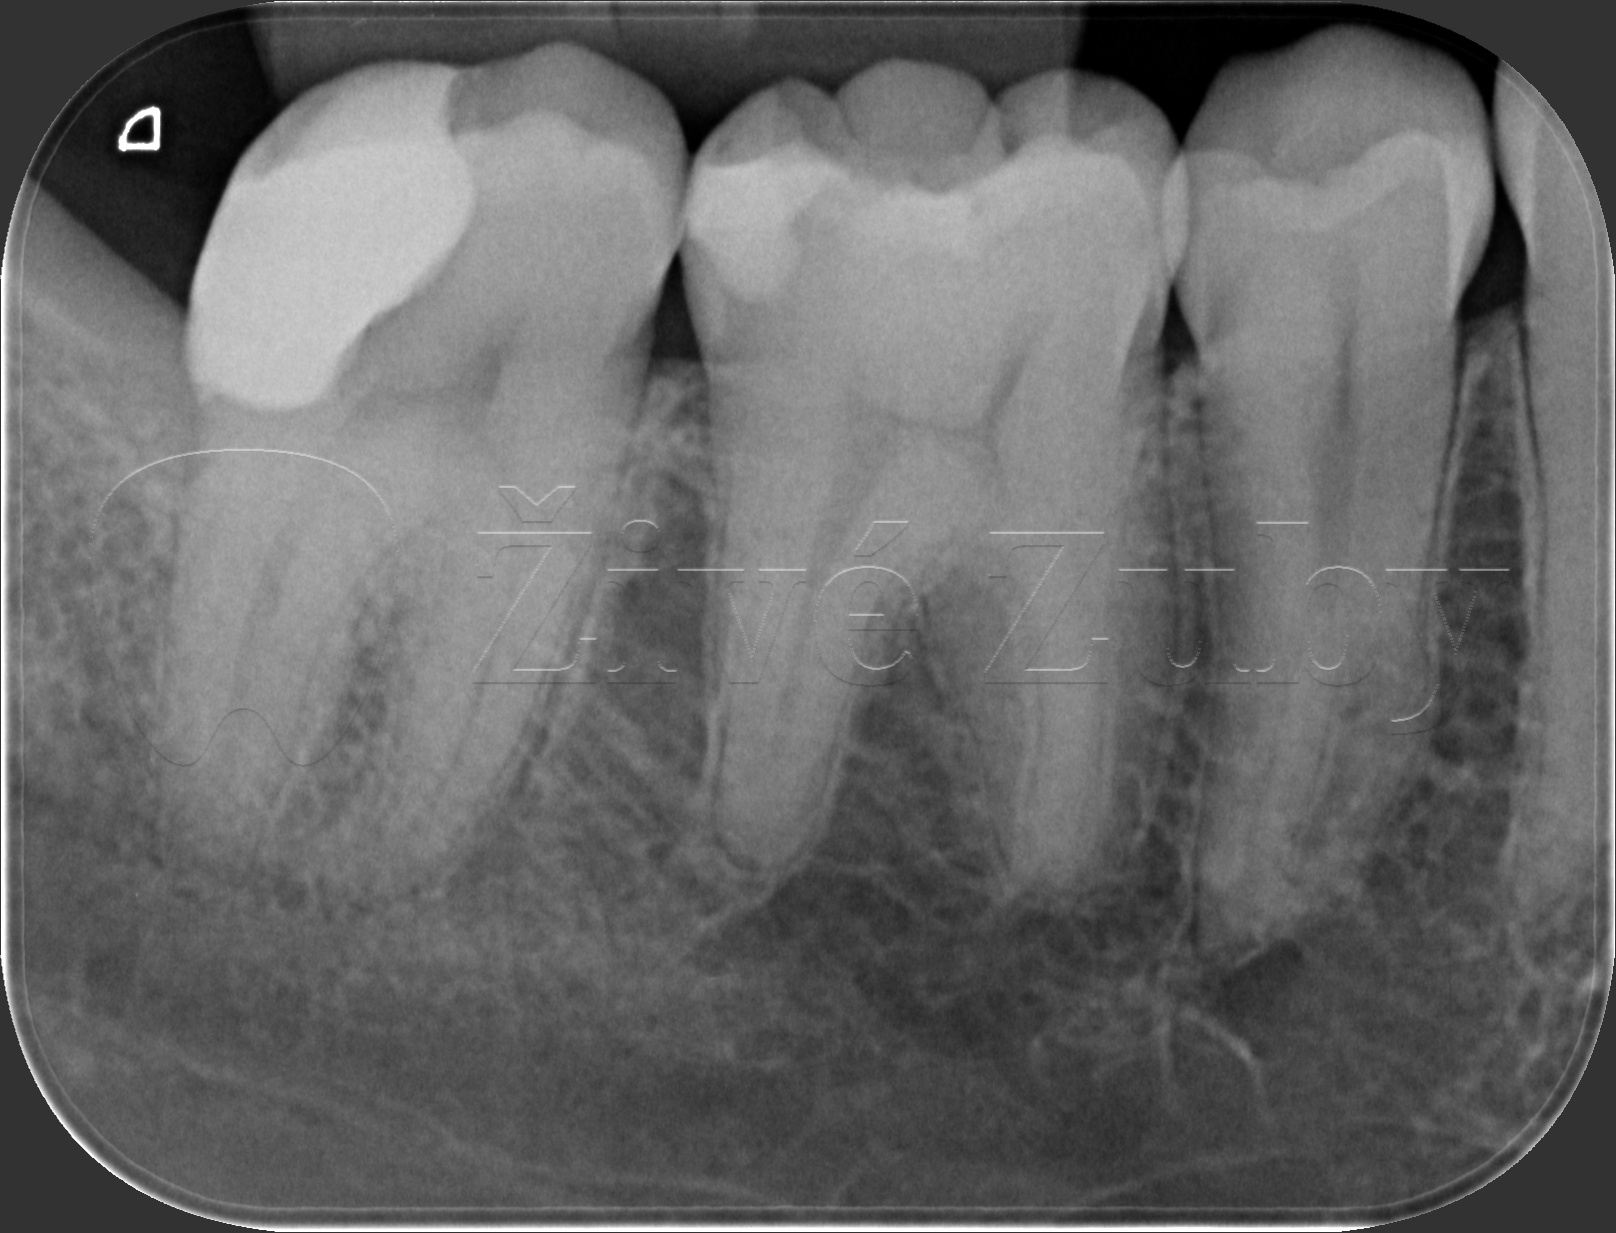

Ošetření hlubokých kazů

Výchozí stav  ——-> Kontrola po 2 letech ——--> Kontrola po 3 letech